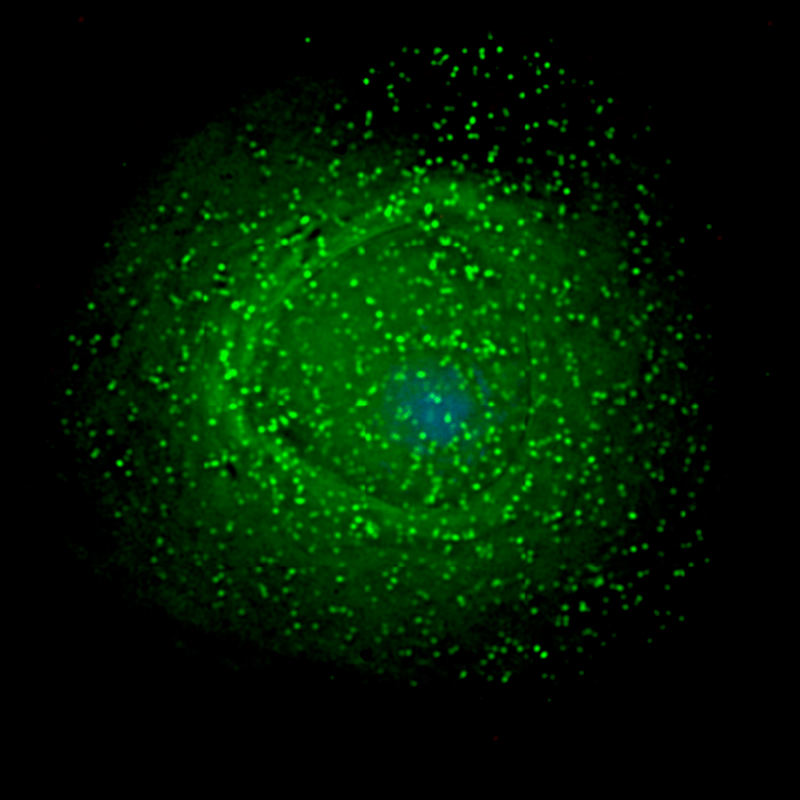

Forma grave de covid-19 pode afetar os olhos, revela pesquisa

Por 16 abr 2021, 20h18 | Atualizado em 22 Maio 2024, 18h24